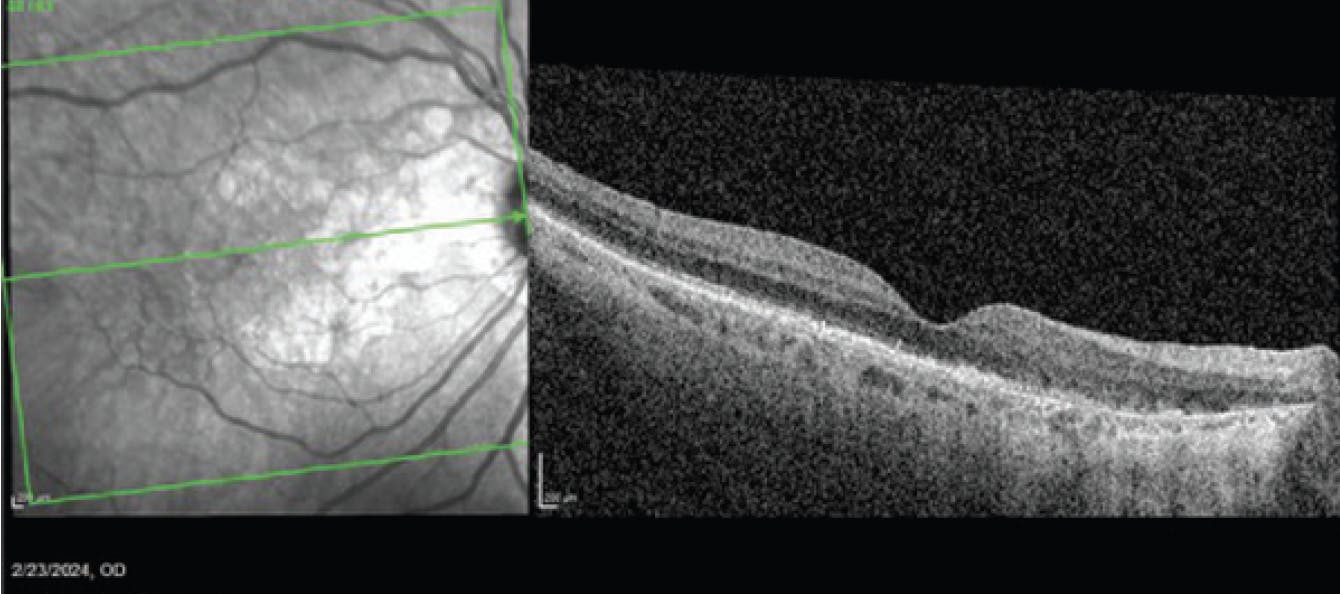

During a January 2024 visit, after 2 monthly injections of avancincaptad pegol, the patient complained of worsening vision OD. On OCT, she was found to have new cystoid macular edema, subretinal fluid, and subretinal hyperreflective material (Figure 4). She was diagnosed with new onset wet AMD and was treated with bevacizumab (Avastin). BCVA at this visit was 20/40. She returned a month later for follow-up, at which time the anatomy had improved, but BCVA was still 20/40 (Figure 5). A second bevacizumab injection was administered.

<p>Figure 4. In January 2024, OCT (right) showed cystoid macular edema, subretinal fluid, and subretinal hyperreflective material consistent with wet AMD.</p>

Figure 4. In January 2024, OCT (right) showed cystoid macular edema, subretinal fluid, and subretinal hyperreflective material consistent with wet AMD.